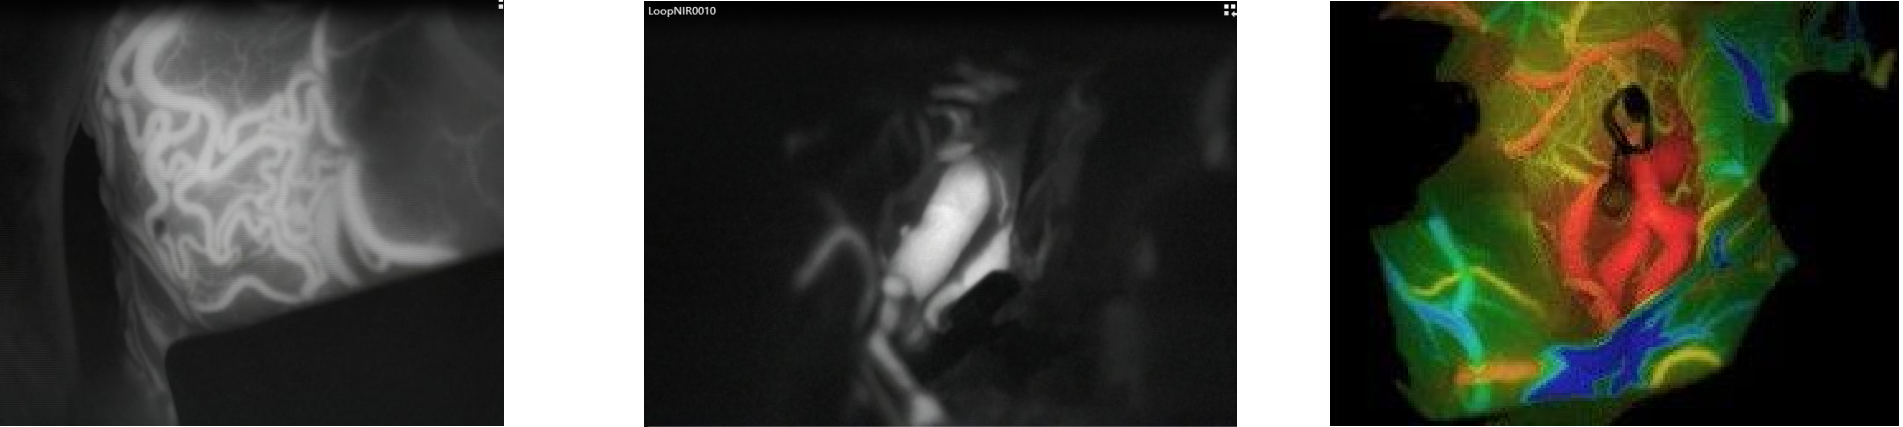

三维影像融合技术

术前将患者头部CT、CTA、MR、MRA、fMR、DSA等影像数据,应用三维影像融合技术,将影像数据进行融合重建,并进行判读、手术模拟。例如:在科室多例脑膜瘤患者成功手术案例中,利用三维影像融合技术,可重点了解肿瘤的供血及肿瘤与大脑中动脉的位置、关系,肿瘤与颅骨的关系,肿瘤在颅内三维坐标的位置,做好术前规划、模拟手术路径。通过术前三维演示、讨论使整个手术团队明白整个手术过程,从而可达到有的放矢、密切配合、减少手术操作过程。

血管荧光造影技术

血管荧光造影技术是近年来一项比较新的技术,它利用术中静脉注入吲哚菁绿,使脑血管术中发出荧光,准确显现出血管走形及形态。血管荧光造影技术已常规应用于科室动脉瘤手术、动静脉畸形及“烟雾病”搭桥手术中,是手术中有用的工具,可提供实时信息,及时检查手术效果,有效减少术后并发症,提高手术的安全性,从而能有效的改善患者预后。